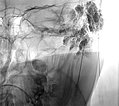

X-ray after direct injection of contrast medium into the venous malformation via 2 puncture needles. No outflow via any communication veins, good needle position for sclerotherapy. Now 2 ml of Aethoxysklerol 3% 1:4 admixed with air (foam sclerotherapy) are injected.

X-ray after injection of contrast medium into the venous malformation during the 2nd sclerotherapy 8 months later. Again no outflow via communicating veins is displayed. Good needle position for another foam sclerotherapy (3 ml Aethoxysklerol 3%, foamed 1:4 with air).

X-ray after injection of contrast medium into the venous malformation, for what is now the third sclerotherapy treatment after pain recurrence. Almost the entire remaining venous malformation is contrasted by contrast injection at the current needle position. Now 4.5 ml of Aethoxysklerol 3%, foamed 1 to 4 with air, is injected.